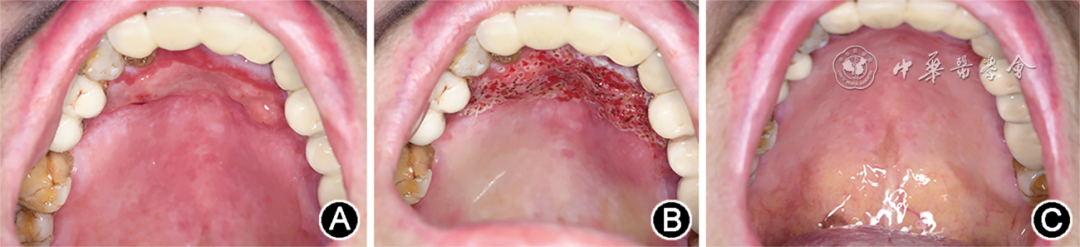

3.口腔专科检查:全口牙龈可见云雾状白纹,11、21—23牙龈缘充血发红,尼氏征阴性;硬腭前份可见4.5 cm×2.0 cm大小的不规则糜烂面伴明显充血,表面覆盖淡黄色假膜,周围黏膜可见白纹;余口腔黏膜未见明显异常(图1)。

▲ 图1 难治性口腔扁平苔藓患者初诊时口内照片 A:全口牙龈可见云雾状白纹,11、21—23牙龈缘充血发红;B:硬腭前份黏膜可见4.5 cm×2.0 cm大小的不规则糜烂面伴充血,周围可见白纹

7.治疗效果及随访:治疗2周后复诊,患者诉疼痛减轻、糜烂缩小(图3A)。再次于局部麻醉下行硬腭前份黏膜充血及糜烂病损半导体激光治疗术,工作功率、工作时间及术后用药同前(图3B)。第2次治疗后2周复查,患者硬腭前份糜烂完全愈合(图3C),且自述无明显疼痛。随访3个月,无复发。

▲ 图3 难治性口腔扁平苔藓患者首次治疗后2周及第2次治疗后2周口内照片 A:首次治疗后2周口内照片示糜烂面积缩小,腭部前份黏膜可见3 cm×1 cm大小的糜烂面伴充血,周围可见白纹;B:首次治疗后2周,对腭部前份黏膜充血及糜烂病损行第2次半导体激光治疗术后即刻;C:第2次治疗后2周口内照片,示腭部前份原糜烂面已完全愈合